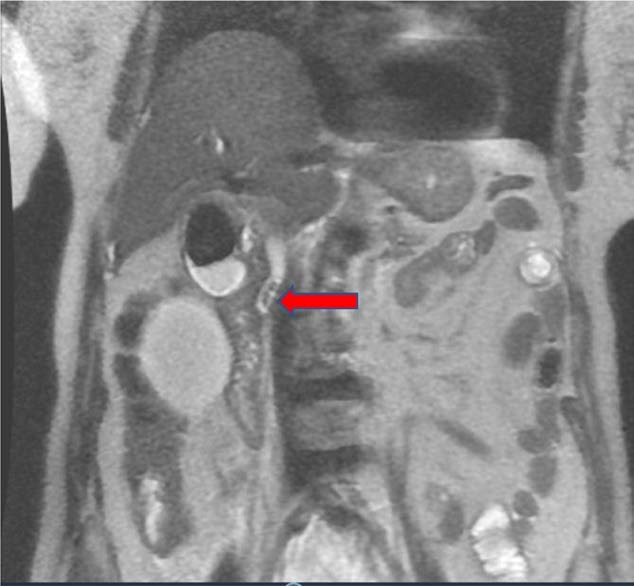

图1 MRI示胆总管扩张(12 mm),近端胆总管内多发充盈缺损(红色箭头),提示嵌顿结石